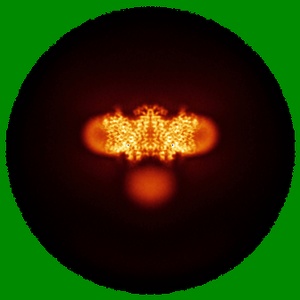

Cryo-EM structure of human Anion Exchanger 1 bound to Dipyridamole

Single-particle3.13 Å

Sample: Dimeric anion exchanger 1 (SLC4A1)